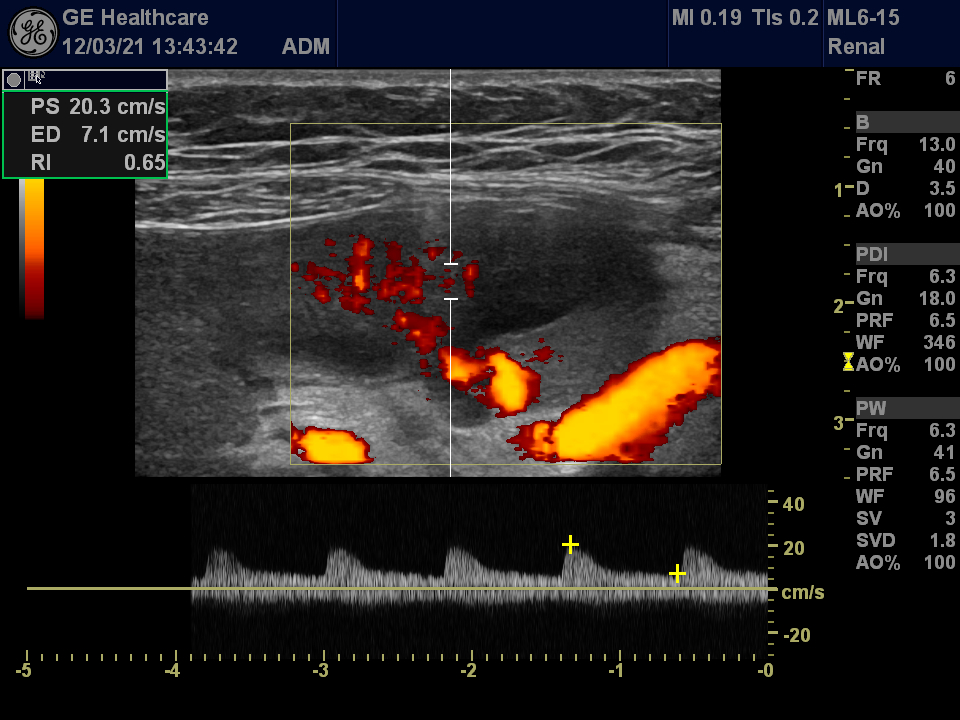

Small infarction of a transplanted kidney Szerző: admin | márc 22, 2012 | CEUS, Renal infarction | Nincsenek hozzászólások wedge shaped hypoechoic area in the transplanted kidney lack of circulation acceleration decreased in the surrounding arteries segmental artery show normal Doppler waveform no vascularisation at all – infarction